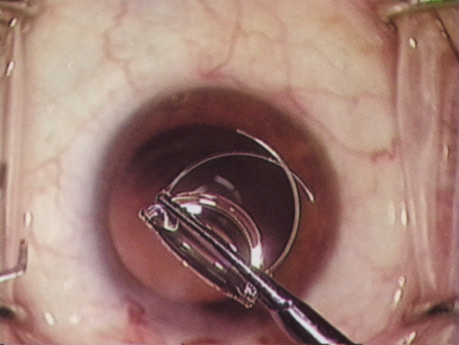

ANTERIOR CAPSULOTOMY

One of the most beneficial techniques developed over the last decade is capsulorrhexis. A continuous curvilinear anterior capsular opening helps prevent intraoperative and postoperative complications. With capsulorrhexis, mechanical strength of the capsular opening is superior to that in a can-opener capsulotomy; thus, a tear to the posterior capsule with subsequent vitreous loss is much less likely.96 Capsulorrhexis allows for nuclear manipulation with less risk of posterior capsule rupture. Cortex removal is made easier as well, because it becomes easier to differentiate cortical material from anterior capsule. Should a posterior capsular tear occur, sulcus fixation is more likely attainable with the presence of a clearly visible residual anterior capsular rim. Placement of both IOL haptics into the capsular bag is more certain with capsulorrhexis because the surgeon can more easily visualize the haptics gliding beneath the anterior capsular rim.

Capsulorrhexis can be performed with a cystitome, capsulorrhexis forceps, or combination-type instruments. Regardless of which instrument is used, several principles can help the surgeon successfully complete capsulorrhexis. It is important to maintain the anterior chamber, because making the chamber shallow increases tension on the zonules and causes the tear to run peripherally. The authors recommend the use of a viscoelastic agent for maintaining chamber depth and, of course, for endothelial protection. Therefore, if the tear begins to run peripherally, the surgeon should redeepen the anterior chamber before attempting to redirect the tear. Additionally, folding the capsule margin can aid the surgeon in redirecting the tear more accurately (Fig. 10).

Fig. 10. The capsulorrhexis tear is more easily redirected by folding the capsule over, in advance of the tear.